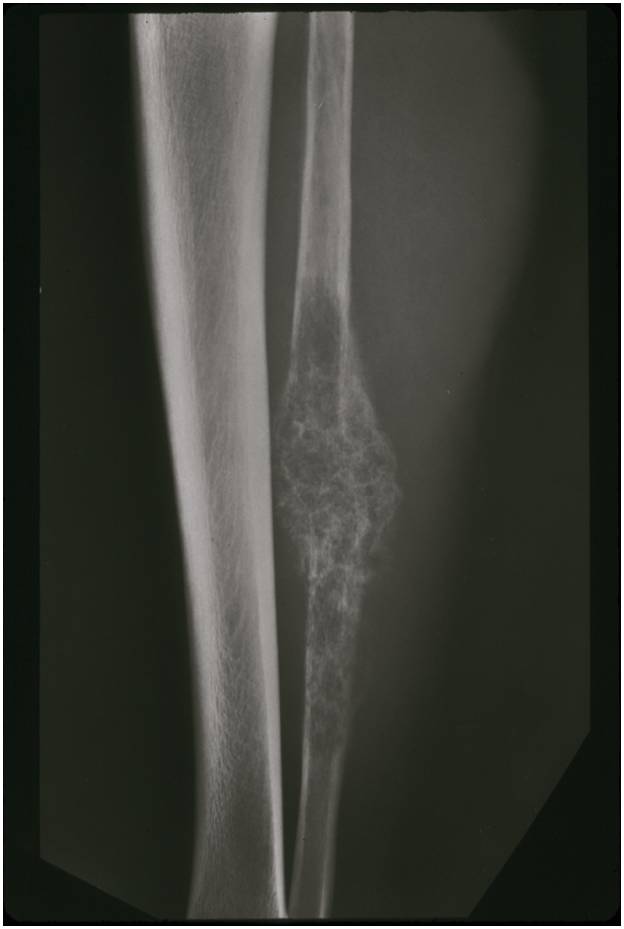

- Aggressive motheaten to permeative lesion

- Indistinct border in most cases

- Osseous destruction with a soft tissue component

- Chondroid matrix calcification may be present (60-70% of cases)

- Soft tissue mass